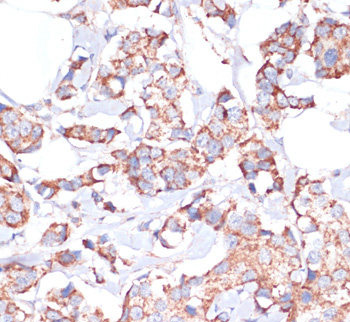

(Immunohistochemistry of paraffin-embedded Human breast cancer using UBE2O Polyclonal Antibody at dilution of 1:100 (40x lens).)